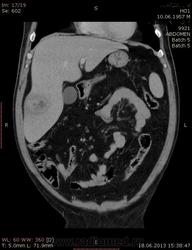

На абсцесс похоже

+1. Контраст вводили?

На мой взгляд, абсцесс.

Тоже за абсцесс.

Cпасибо , коллеги.Сегодня больного прооперировали диагноз абсцесс правой доли печени.Оказывается больной когда - то получил тупую травму живота, об этом нам не говорил.....